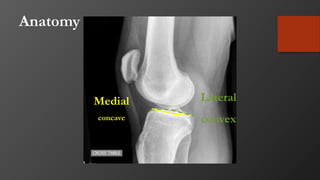

Anatomy

• Consist of medial and lateral

plateau

• Medial larger

• Medial lower (concave)

• Medial bone harder (thus

less likely to fracture)

• Lateral higher (convex)

• Lateral cartilage thicker

Medial

concave

Lateral

convex